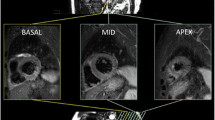

CMR was performed during the index admission on a 1.5T scanner (Siemens Avanto, Erlangen, Germany [n = 4] or Philips Intera, Best, The Netherlands [n = 6]) or 3.0T scanner (Siemens Skyra, Erlangen, Germany [n = 5]; Philips Achieva TX, Best, Netherlands [n = 4] or GE Signa HDxt, Little Chalford, UK [n = 1]) with retrospective electrocardiographic gating and dedicated cardiac receiver coils. The imaging protocol is outlined in Figure 1 and Additional file 1. T2w-STIR imaging with coil SI correction, cine imaging with steady state free precession and Late Gadolinium Enhancement (LGE) imaging were performed in long-axis views and contiguous short-axis slices covering the entire LV. LGE images were acquired 10–15 minutes after administration of 0.15 mmol/kg (3.0T) or 0.2 mmol/kg (1.5T) gadolinium-DTPA (Magnevist, Bayer, Germany) using a segmented inversion-recovery gradient-echo sequence. The inversion time was progressively adjusted to null unaffected myocardium.

CMR protocol (for Siemens Avanto 1.5T scanner; parameters for other scanners presented in Additional file 1 ). 4C, 2C, 3C = 4,2,3-chamber long-axis views, LV = left ventricle, SAX = short-axis, FOV = field of view, AAR = area at risk, IS = infarct size, IMH = intramyocardial haemorrhage, MVO = microvascular obstruction.

IS and AAR quantification

Image quality was graded according to a 4-point scale before analysis: 3 = excellent, 2 = good, 1 = moderate and 0 = unanalysable. To remove the confounding variable of image quality on AAR quantification, 26% of studies from the total study population, where T2w-STIR images were deemed non-analysable were excluded from the random number study selection pool. Analysis was performed offline in a central core lab, blinded to patient details using cmr42 (Circle Cardiovascular Imaging, Calgary, Canada). LGE, T2w-STIR and cine images were studied together and co-registered to allow accurate quantification based on all available data. For the assessment of LV volumes and function, IS and AAR, endocardial and epicardial borders were manually contoured on contiguous short-axis LV slices, excluding papillary muscles, trabeculae, epicardial surfaces and blood-pool artefact, and the quantification method applied. The most apical LGE and T2w-STIR slice was excluded to minimize partial volume effect. Total IS and AAR were expressed as percentage of LV mass (LVM).

IS quantification

IS was quantified on LGE magnitude images as hyperenhancement using 5/6/7/8 SD thresholding, FWHM [8] and OAT by 2 experienced readers (JNK, SN: 3 years experience each). Mean IS was compared using the techniques and with manual (visual) quantification. As there is no gold standard technique for in vivo IS quantification, we used the mean of 6 analyses (manual quantification undertaken twice each by observers JNK and SAN, and by an SCMR Level 3 trained reader [GPM: 10 years experience]). Manual quantification has been used in this capacity in the majority of studies comparing quantification methods for IS [6,19,20] and AAR [13,21,22], and has high intraobserver and interobserver agreement and reproducibility [6,14]. For 5/6/7/8 SD thresholding, a region of interest (ROI) was manually drawn in remote (no enhancement, oedema or wall-motion abnormality) myocardium and the area of enhancement automatically calculated as the region with signal intensity 5/6/7/8 SD above the mean within the ROI respectively. For the FWHM technique, an ROI was manually drawn in the infarct core and enhancement calculated as pixels where signal intensity exceeded 50% of the automatically determined maximum signal intensity in the infarct core. Where it was not obvious which ROI in the infarct core had the highest maximum signal intensity, ROIs were drawn in potential regions and the ROI with the highest signal intensity selected. The ROI size for the 5/6/7/8 SD and FWHM methods was set at 2 cm2. The FWHM method is unaffected by ROI size as it selects the threshold based on the single pixel with highest signal intensity. The same signal intensity threshold was set for all slices on 5/6/7/8 SD and FWHM thresholding. OAT automatically calculates a unique signal intensity threshold for each slice by dividing the greyscale signal intensity histogram in each slice into 2 groups (enhanced, normal) based on the signal intensity threshold giving the least intraclass variance (lowest sum of variances) and thus most homogeneity of signal intensities within each group (Figure 2) [11,12]. The only user input, and thus potential sources of variation are the endocardial and epicardial contours, and manual correction of noise artefact. OAT requires no ROI selection and is thus largely user-independent compared with SD-based, FWHM and manual quantification.

Otsu’s Automated Thresholding (OAT) method. Top row: Short-axis late gadolinium images from basal to apical (left to right). Middle row: Enhancement (yellow) signifying infarct, designated on a slice-by-slice basis by OAT method. Bottom row: OAT automatically identifies hyperenhanced areas by selecting the grayscale signal intensity threshold (red) on a slice-by-slice basis that gives the minimal intraclass variance within enhanced and normal myocardium.